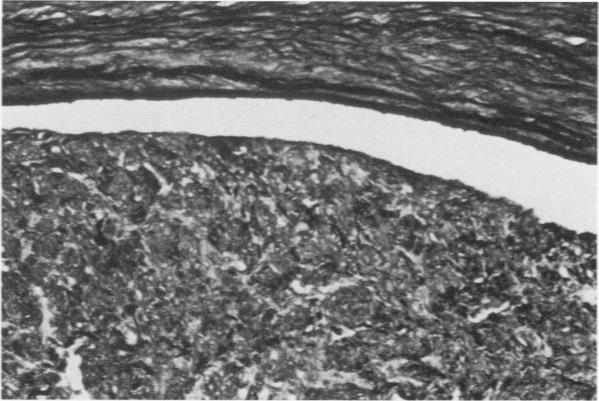

Cells derived from human atherosclerotic plaques and from arterial media were compared with cells obtained from human leiomyomata and myometrium with respect to growth behavior in long-term cell culture. None of numerous variations in culture media, including alterations of serum concentration and source, improved the rate of cell multiplication or in vitro longevity. Both uterine cell types, but neither arterial cell type, multiplied after tissue dissociation with enzymes (elastase, collagenase, hyaluronidase). The replicative life-span of each of eight samples of arterial plaque cells was equal to or less than that of the corresponding medial cells. A similar relationship was observed for eight paired sets of leiomyoma and myometrial cells. The results indicate that, under the conditions of culture in vitro, cells of a bona fide smooth muscle tumor have a finite replicative life-span and smooth muscle cells of atherosclerotic plaques behave in a similar manner.

就长期细胞培养中的生长行为而言,将源自人类动脉粥样硬化斑块和动脉中层的细胞与源自人类平滑肌瘤和子宫肌层的细胞进行了比较。在包括血清浓度和来源改变在内的多种培养基变化中,没有一种能提高细胞增殖率或体外存活时间。两种子宫细胞类型在经酶(弹性蛋白酶、胶原酶、透明质酸酶)解离组织后都会增殖,但两种动脉细胞类型都不会。八个动脉斑块细胞样本中每个样本的复制寿命等于或小于相应中层细胞的复制寿命。八对平滑肌瘤和子宫肌层细胞也观察到类似关系。结果表明,在体外培养条件下,真正的平滑肌肿瘤细胞具有有限的复制寿命,动脉粥样硬化斑块的平滑肌细胞表现方式类似。